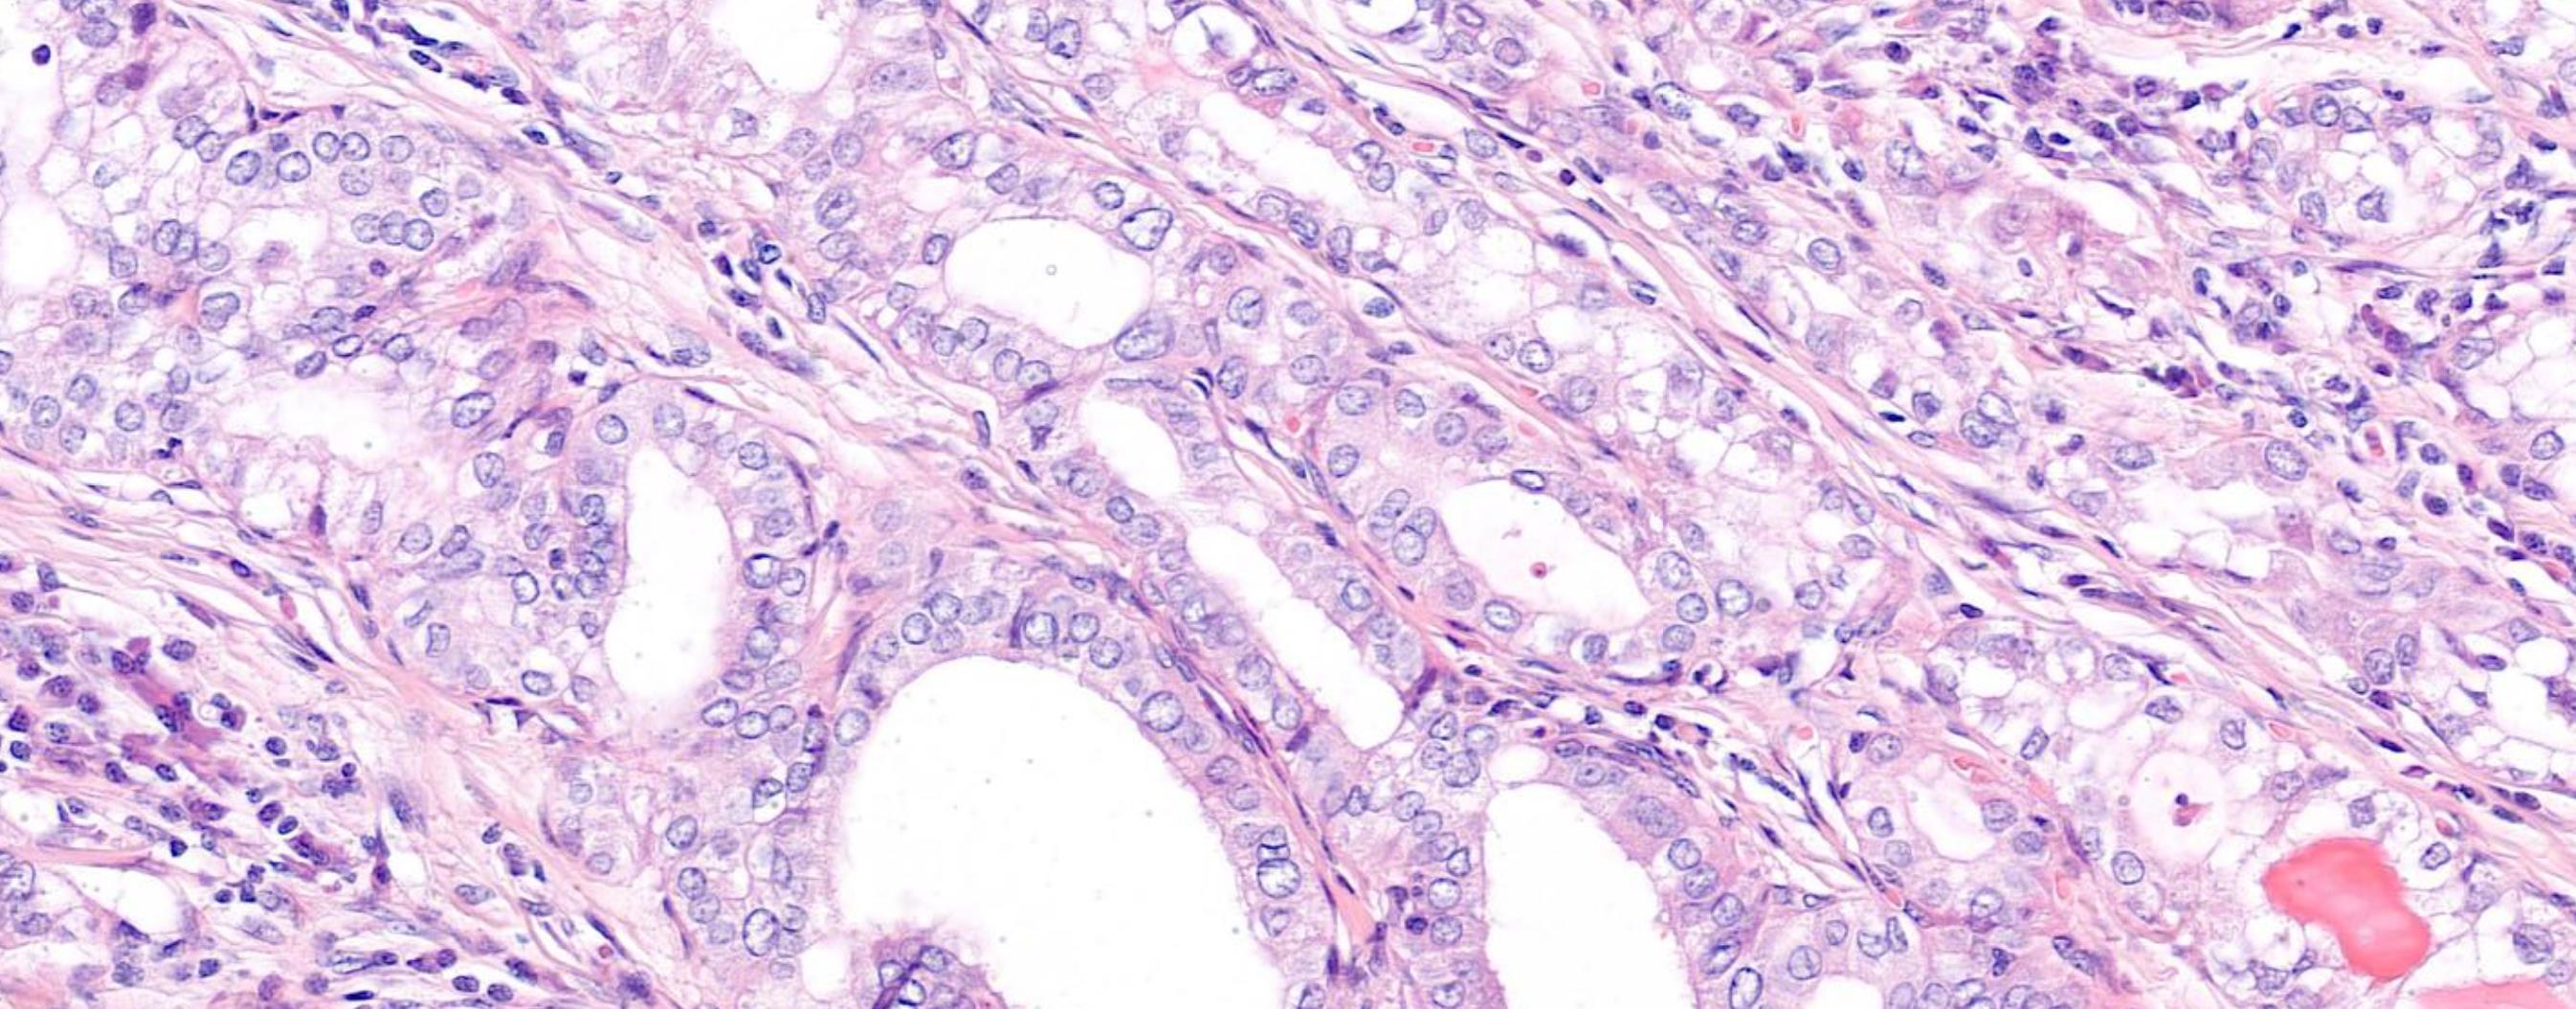

Female 51 years Thy 3a left hemithyroid.

Case 8 Diagnosis

Poorly differentiated thyroid carcinoma arising possibly in a columnar cell variant of Papillary thyroid carcinoma

Discussion-Follicular-derived carcinomas, high-grade Subtypes • Poorly differentiated thyroid carcinoma (PDTC)- Insular carcinoma • Differentiated high-grade thyroid carcinoma (DHGTC) Turin consensus criteria for PDTC (i) presence of a solid/trabecular/insular pattern of growth in a tumour diagnosed as malignant based on invasive properties; (ii) absence of conventional nuclear features of papillary carcinoma; (iii) presence of at least one of the following: convoluted nuclei, mitotic count ≥ 3 per 2 mm2 , tumour necrosis DHGTC- ≥ 5 mitosis per 2 mm2 in hot spot + tumour necrosis, at least partially preserved normal tumour histology and immunoprofile

Immunoprofile • Positive for keratins, thyroglobulin, TTF1, and PAX8 • Thyroglobulin expression is typically reduced

• Ki67/MIB-1 usually 10-30%

and focal in poorly differentiated areas often with a peculiar dot-like paranuclear pattern.